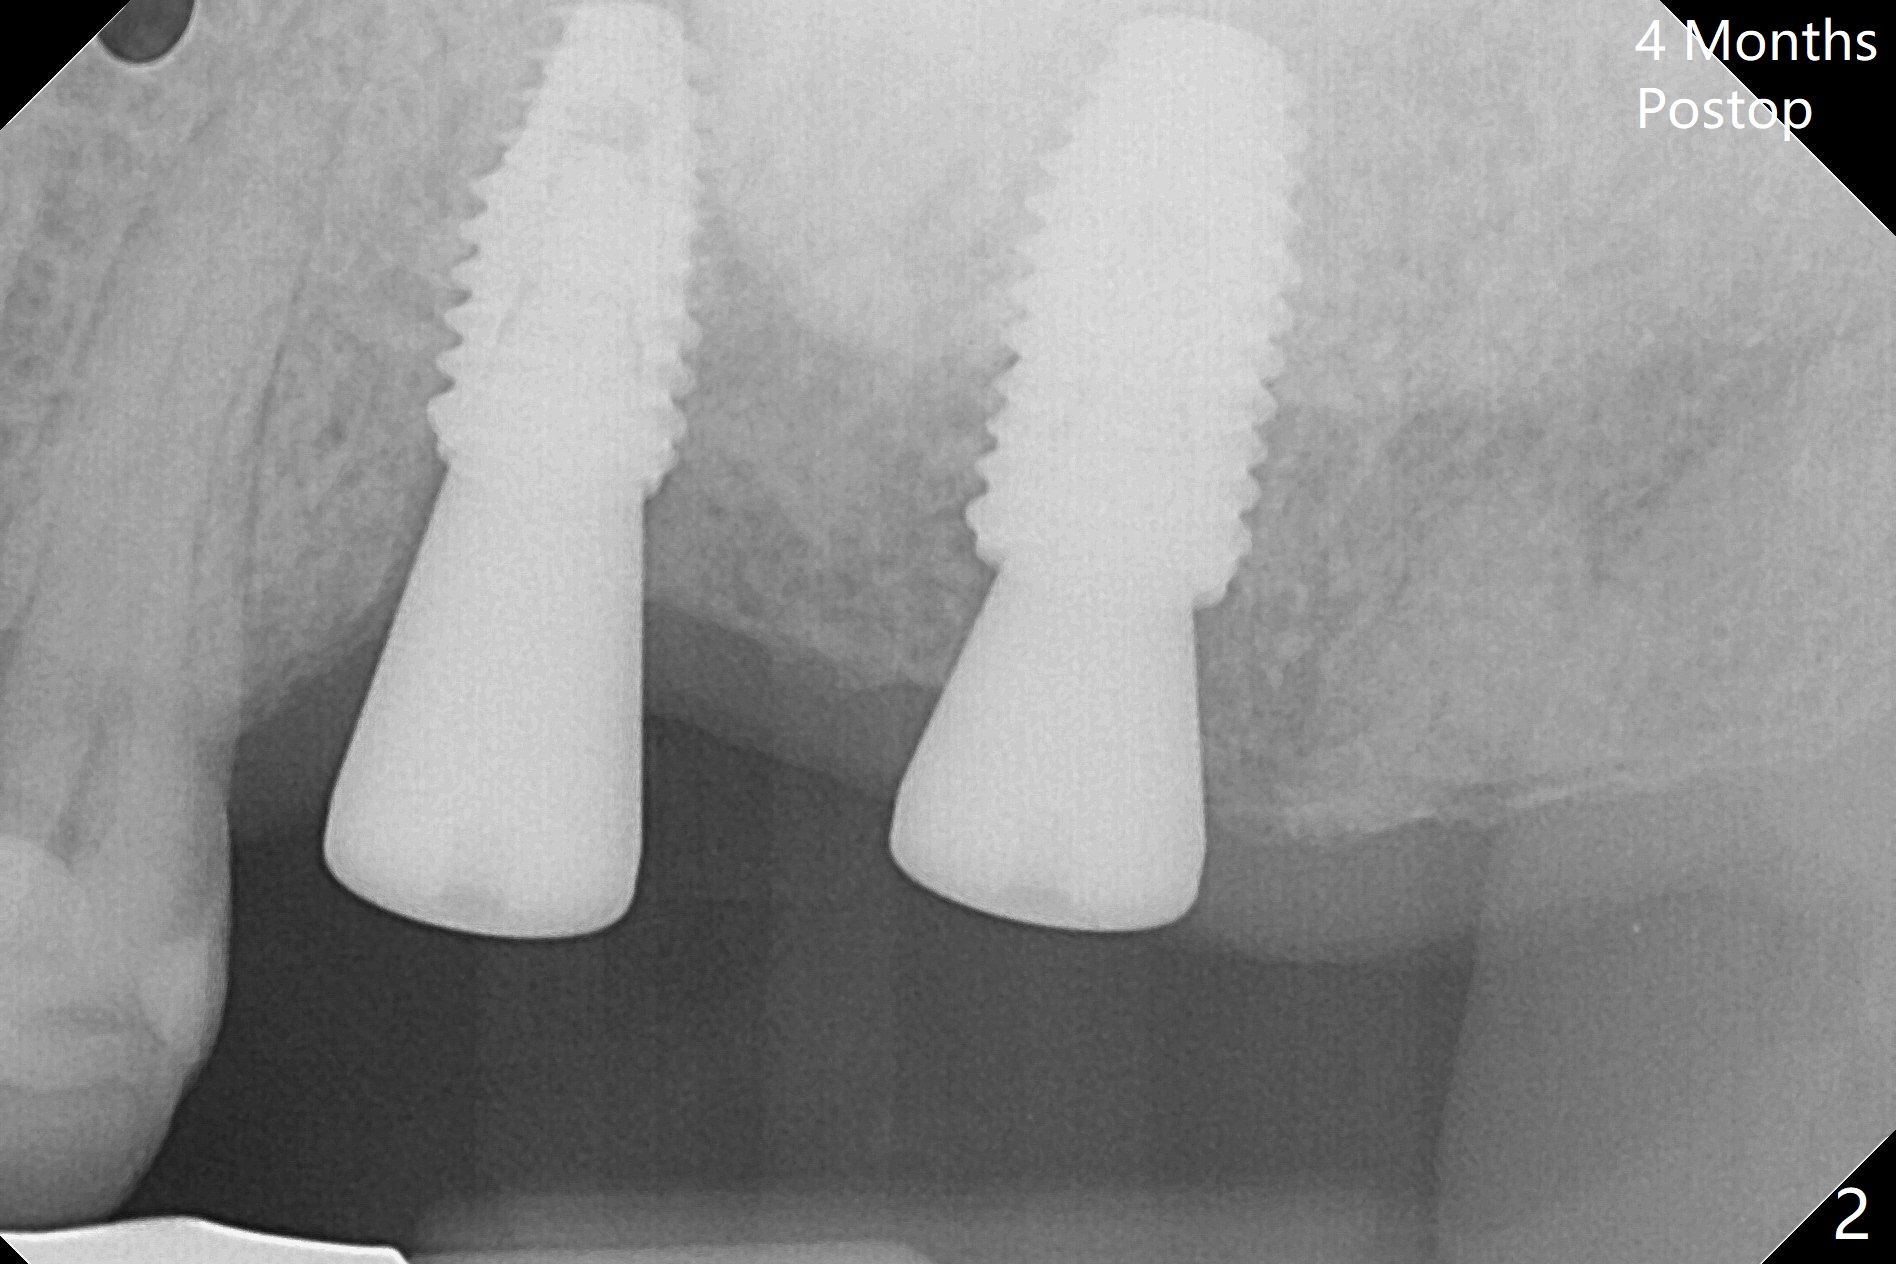

With one carpule of 2% Xylocaine with 1:100,000 Epinephrine, there is no intraop pain associated with placement of 2 implants with guide (Fig.1). Postop pain is minimal. Difficulty is high torque in insertion. At the site of #15, there is no bone shaving associated with 4 mm or less drills. The deeper portion of the bone seems to have denser bone. In spite of using 5 mm tap, which is not recommended, the insertion torque is so high that the implant has to be backed up several times before placement with ~ 50 Ncm. Bone profile is used at #14 before placement of a 5.5x7 mm healing abutment. The healing abutment at #15 dislodges 3 weeks postop and changes to a 5.5x5 mm one. No bone loss is observed 4 months postop (Fig.2). After failure to deliver crowns using impression coping, abutments are placed. The one at #15 is incompletely seated (Fig.3 <) probably due to the contact with the distal crest (*). Change to a smaller one results in complete seating (Fig.4). Cementation of the crowns with access holes is related to no residual cement (Fig.5).